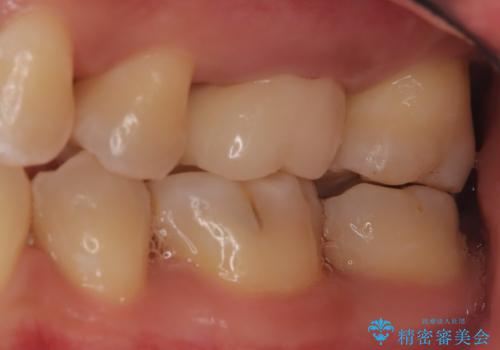

【見逃し根管を発見】根管治療〜セラミッククラウン

- 他院で根管治療した歯の再治療を希望されて来院されました。

未処置の根管があったため、マイクロスコープにて観察したことで、見逃しの根管を含めて清掃・充填を行うことができました。

上顎第一大臼歯は基本的に4根管です。